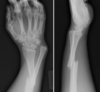

Colles’ fracture

**Colles - ‘dinner fork type deformity’** Features of the injury 1. Transverse fracture of the radius 2. 1 inch proximal to the radio-carpal joint 3. Dorsal displacement and angulation of the distal radius

34

**Smith's fracture (reverse Colles' fracture)** 1. Volar angulation of distal radius fragment (Garden spade deformity) 2. Caused by falling backwards onto the palm of an outstretched hand or falling with wrists flexed

Colles vs Smith fracture

Colles fracture ## Footnote Typically FOOSH forwards Extra-articular radial # with dorsal (posterior / back of hand) angulation and displacement

Smith Fracture ## Footnote Typically FOOSH back of hand Extra-articular radial # with volar (anterior / palmar) angulation and displacement